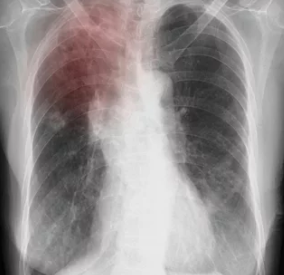

5. 폐결핵이 의심될 때 받는 검사

검사 목적

| 흉부 X-ray | 폐 병변, 섬유화, 공동 등 확인 |